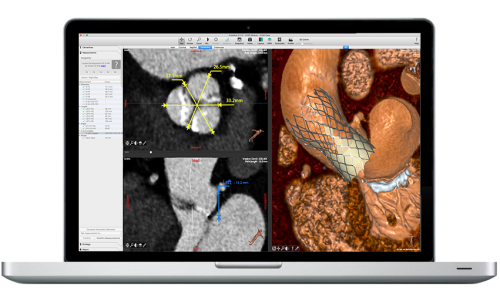

Додаткова мобільна ангіонавігаційна робоча станція EndoNaut зі спеціальним програмним забезпеченням для проведення ендоваскулярних процедур на нижніх кінцівках та в аорто-клубовій області.

Повний пакет програмного забезпечення для кардіосудинної застосувань, у т. ч. цифрова субтракційна ангіографія (DSA), ангіографія з максимальним контрастуванням (MSA) і картируванням (RSA), Pixel Shift / Landmarking, частота 25 кадрів за секунду, використання як традиційних контрастних речовин, так і СО2.